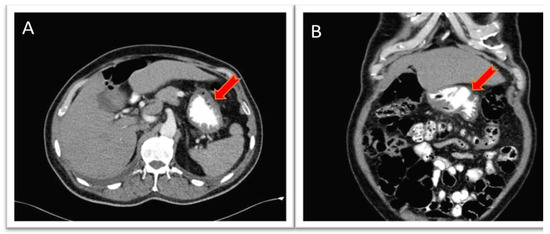

| Diagnostic aids | MRI of face and neck with contrast showing irregular enhancement measuring approximately 25 × 25 × 16 mm in pharyngeal mucosal space involving right palatine tonsil and base of tongue | PET CT * showing hypermetabolic nodule of right pharynx and palatoglossal arch measuring 22 × 10 mm | Endoscopy: moderate, active, non-atrophic chronic gastritis; no malignant neoplasia; Entero-MRI: distended stomach with compact image inside, nonspecific thickening of jejunal loops; contrast-enhanced abdominal CT |